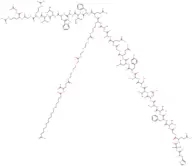

Semaglutide sodium

Proprietà chimiche